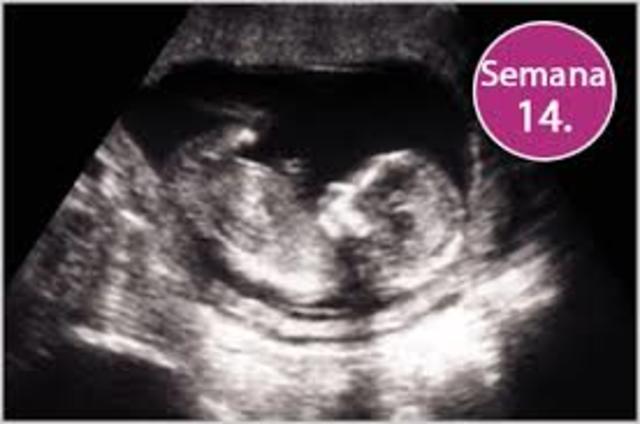

• Semana 14

Semana 14

-Se producen movimientos oculares.

-Se determina el patrón del cabello del cuero cabelludo.